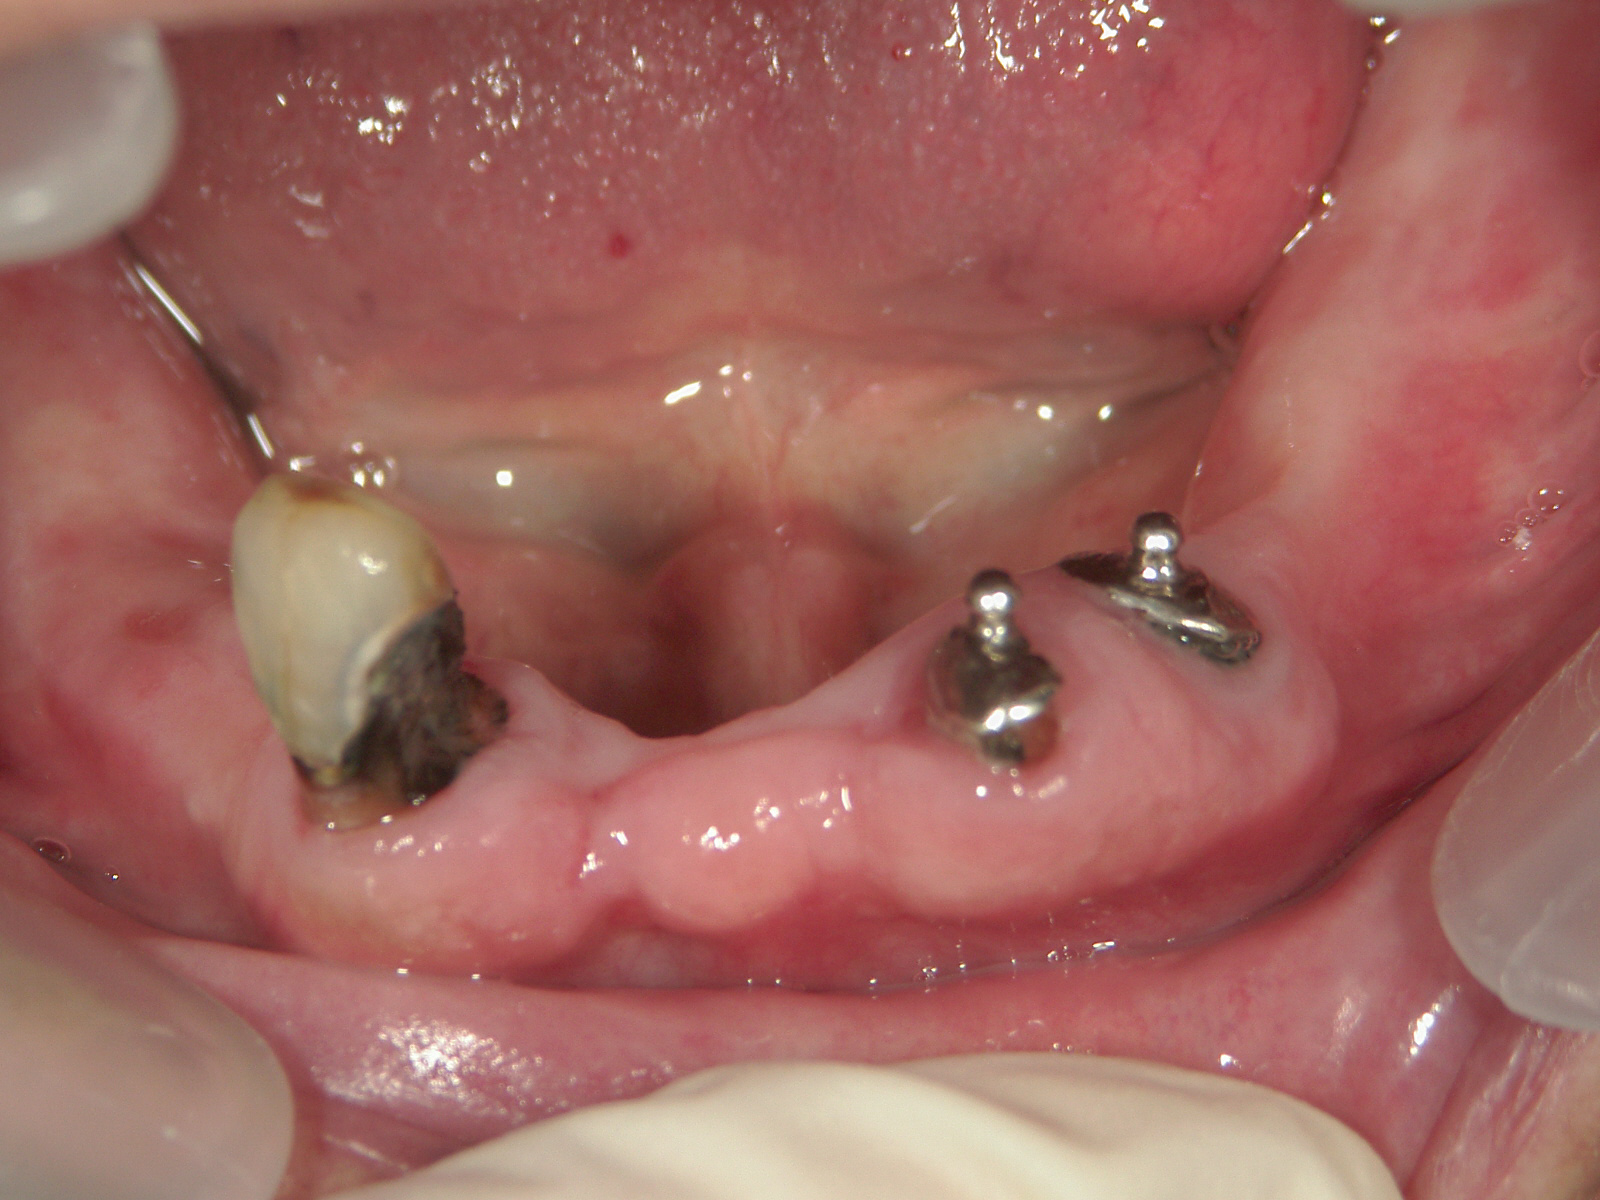

左のように歯茎の近くが酸蝕されますのでご注意くださいね♥